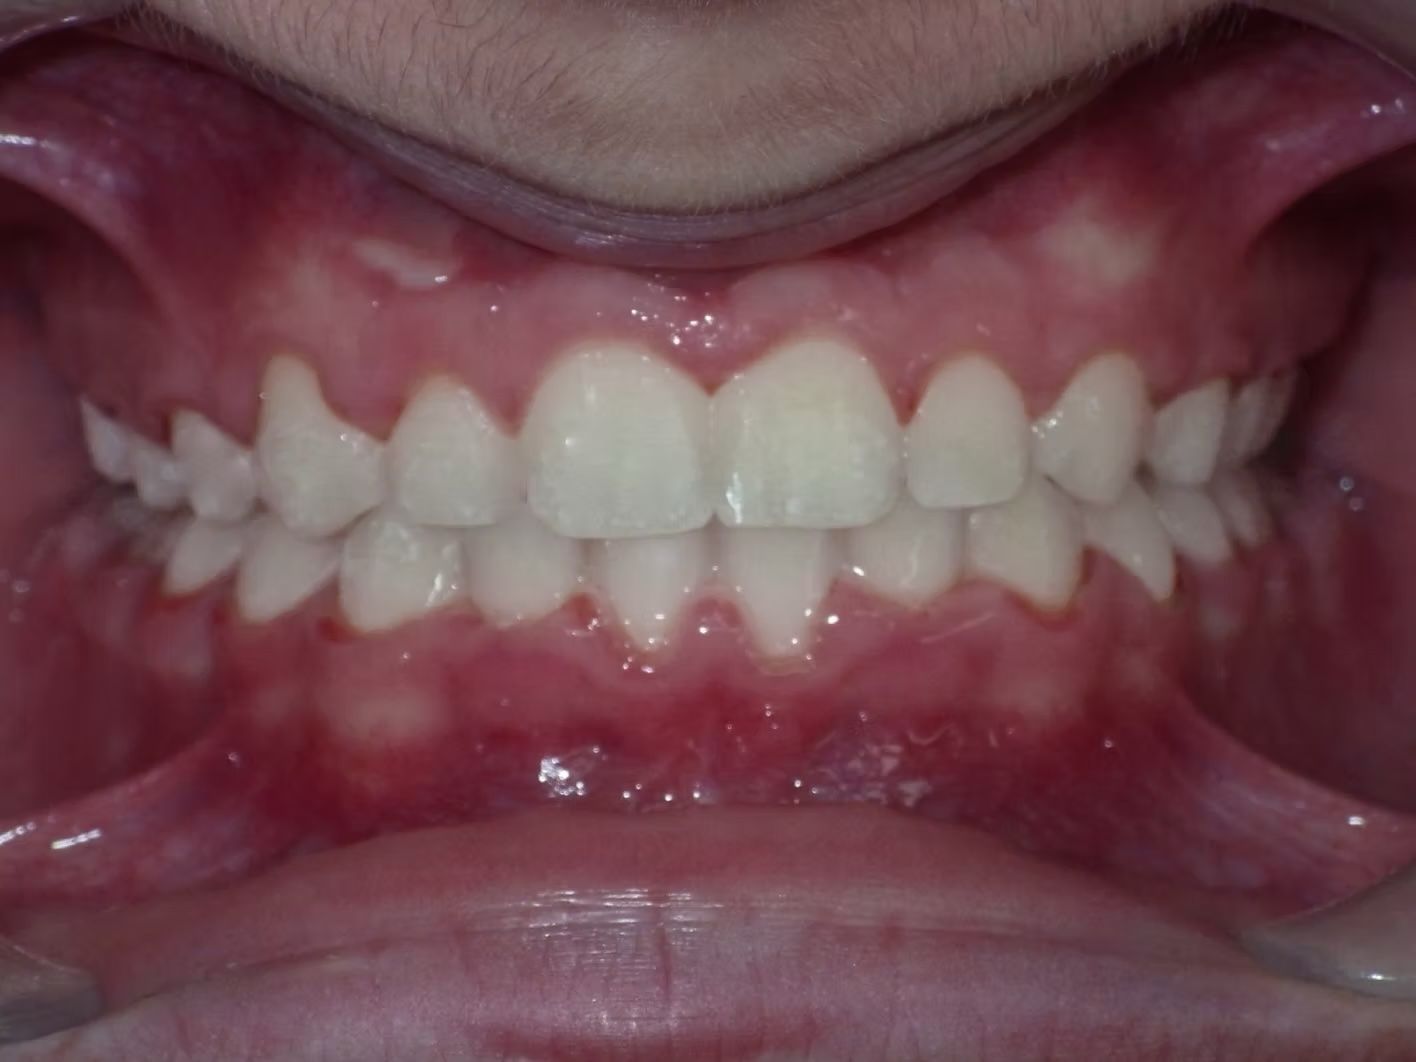

Imset

Imset came to see Dr. Bret because he felt like the upper and lower teeth were too crowded. The lower canines were in cross-bite with the upper teeth and there was significant crowding in the lower arch. He previously had 2 teeth pulled in the top and at the time none in the bottom. This made the top jaw smaller than the lower and the lower teeth didn't have room to fit inside the top teeth. We had 2 lower teeth extracted, and then aligned the upper and lower teeth to fit excellently together- no more crowding!